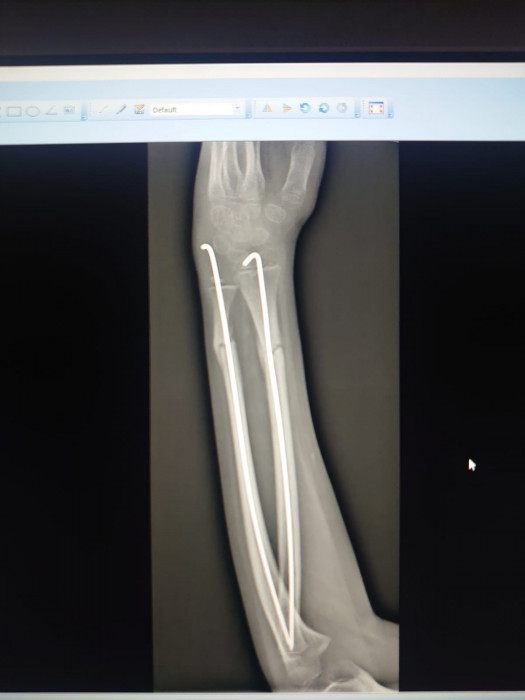

Кораблёв С.Г.: Я забыл сказать, что немного неправильно выбрали тип операции. Соответственно, здесь они поставили спицы, видите, но полностью сопостава не было. И там была еще ошибка, видимо, студенты удаляли, и после этого резко дёрнули, и перелом съехал в это положение. Это после операции. Они сказали: «Давайте подождем». И вот их выписали. Я смог забрать пациента себе, и вел на реабилитацию, поменял гипс, стянул, и мы каждый день работали-работали. И потом я с вашим методом познакомился.

Суриков В.П.: Настолько ровно получилось.

Кораблёв С.Г.: Ну вот факт, такой есть факт. То есть здесь не просто перелом, то есть еще спицы сделали, он ходил с ними, сняли, съехало, и угловая деформация еще больше стала. И сейчас уже такой результат.